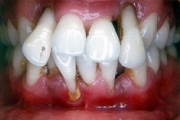

Agressiivne parodontiit

Seda parodontiidi vormi esineb umbes1%-l elanikkonnast. On haiguse kiiresti progresseeruv vorm, mille puhul patsiendid kaotavad kõik hambad enne30-35. eluaastat. Tavaliselt haigestutakse piimahammaste lõikumise ja puberteedi vahele jääval perioodil. Jagunemine:- lokaliseeritud agressiivne vorm- Loe edasi »